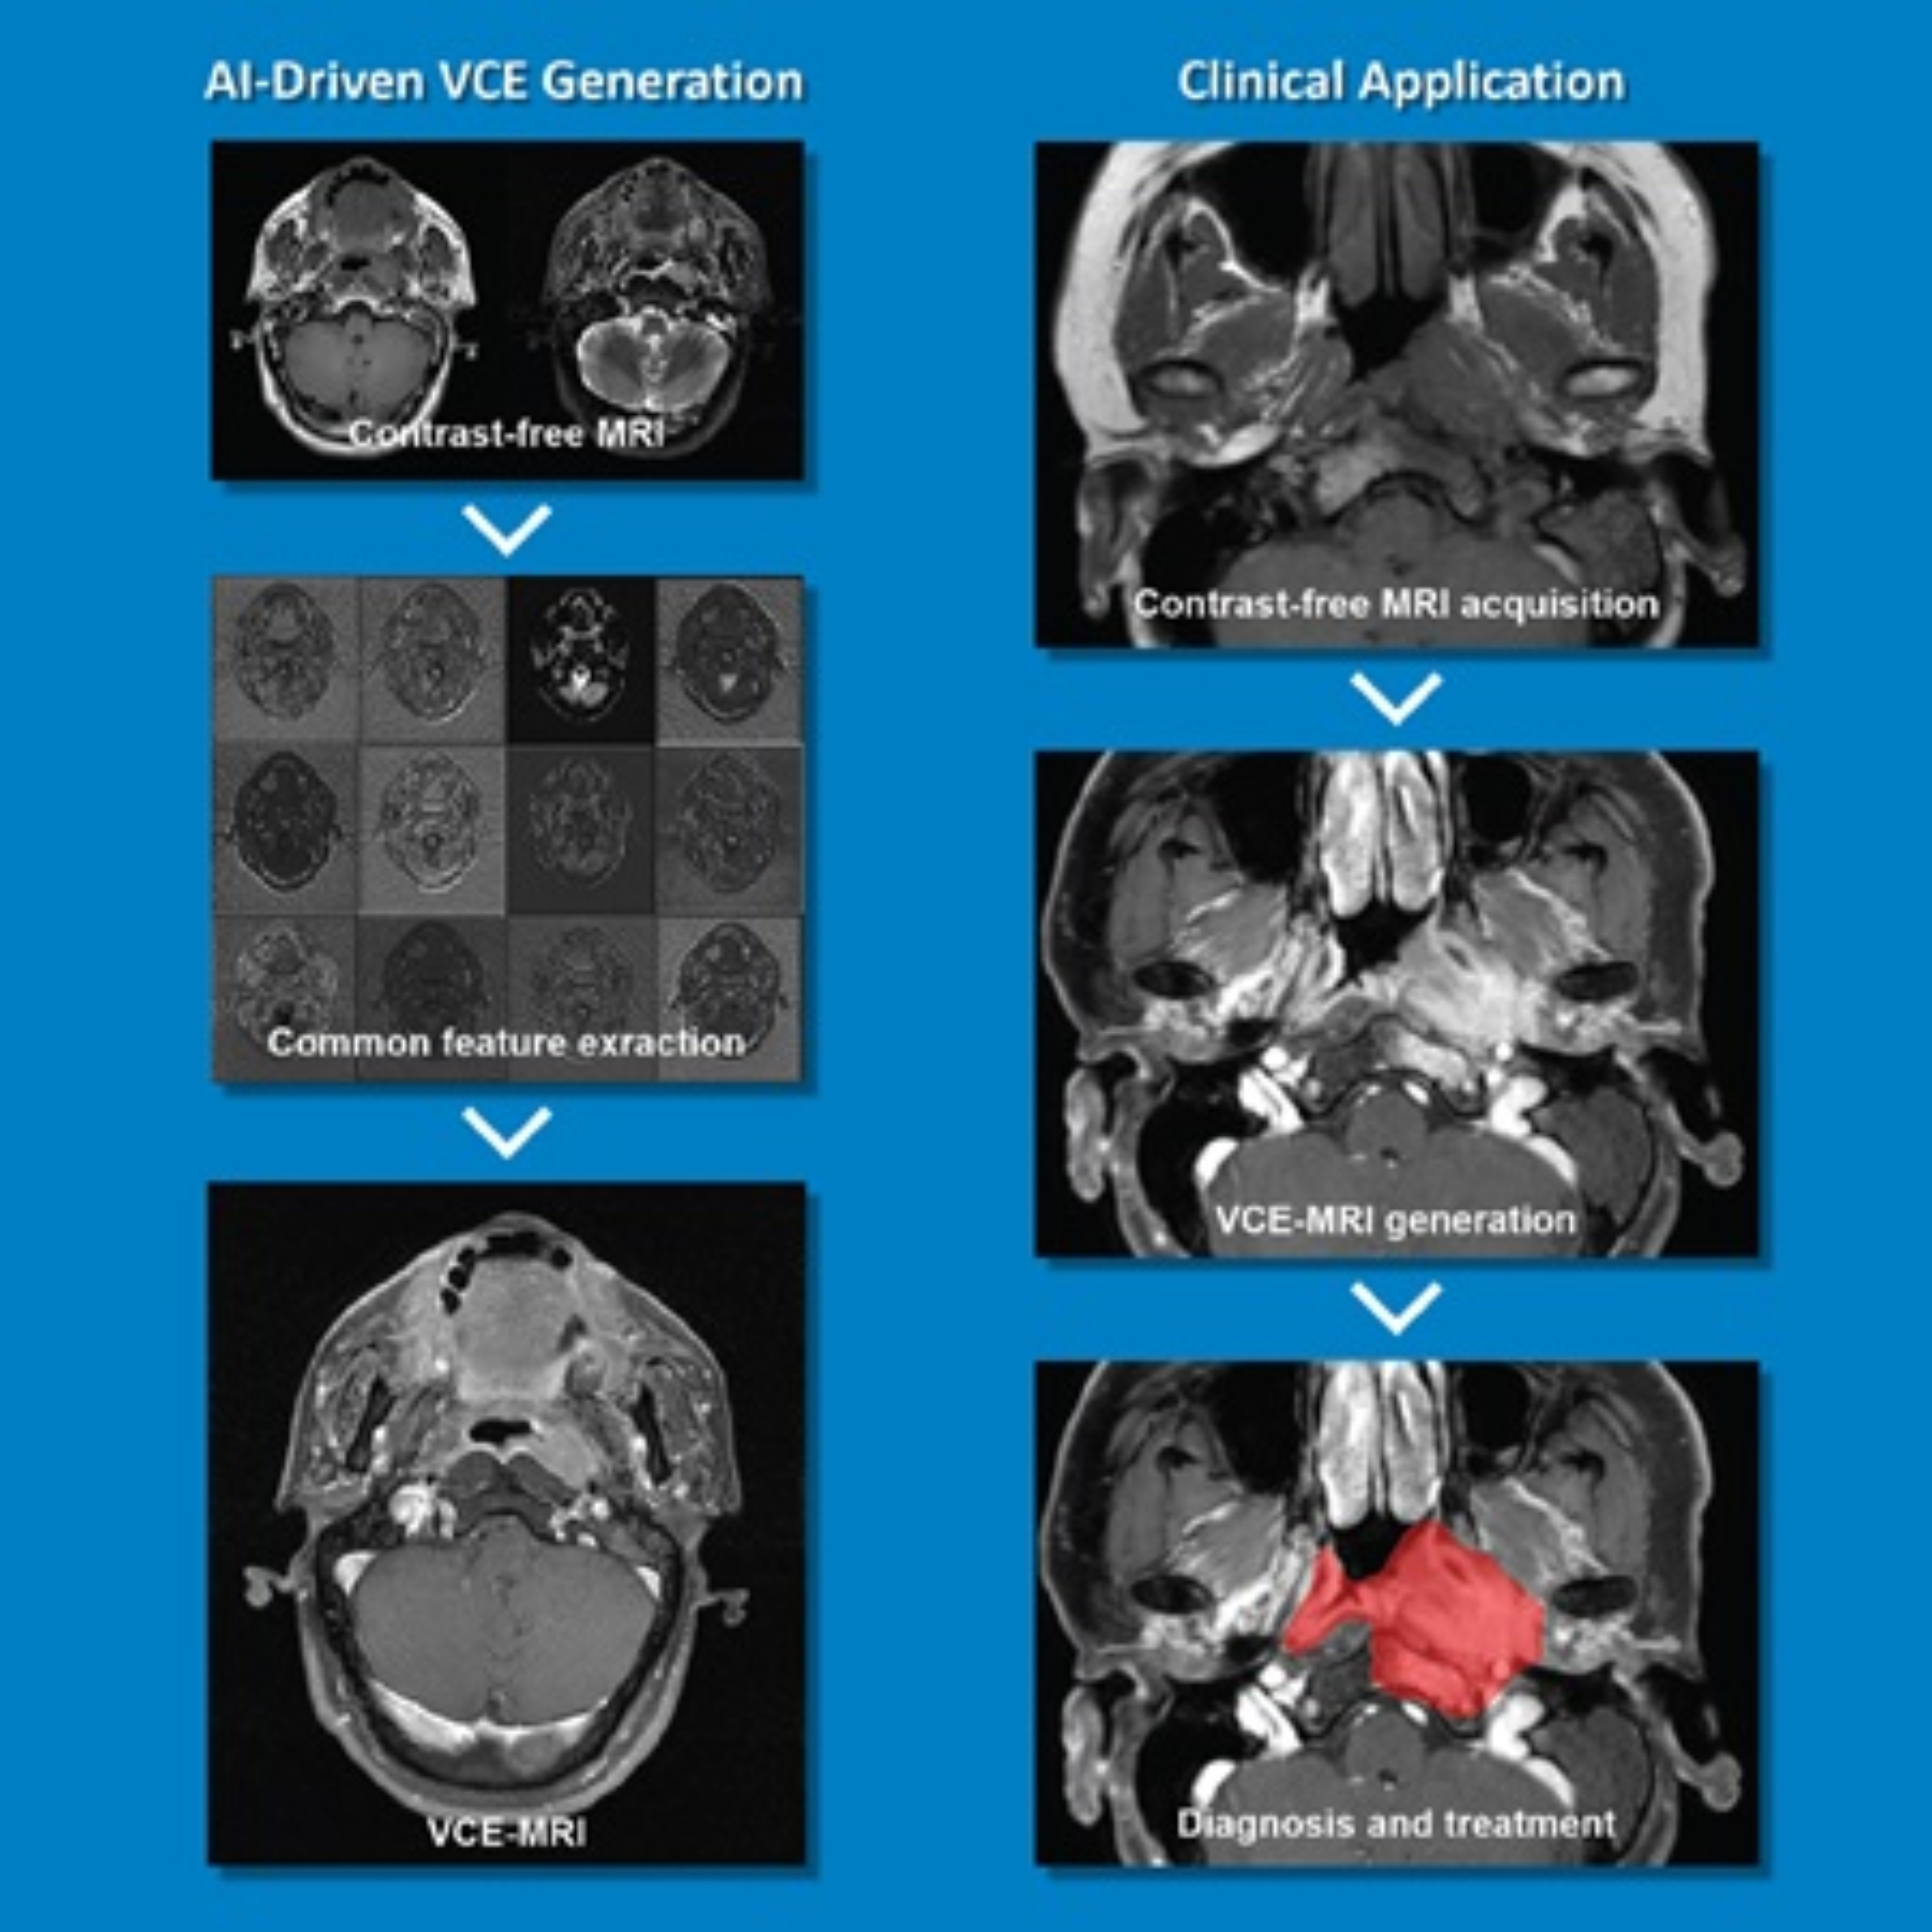

Prof. CAI Jing, Management Committee Member of the Research Institute for Smart Ageing (RISA), Associate Dean of the Faculty of Health and Social Sciences and Professor in the Department of Health Technology and Informatics, developed a Contrast-Free Virtual Enhancement MRI System that revolutionises the precision of tumour treatment by providing high-resolution imaging without the use of contrast agents.

The system leverages advanced algorithms and innovative imaging techniques to precisely visualise tumours, thus facilitating treatment planning and accurate monitoring. The system offers advantages in terms of patient safety, cost-effectiveness and enhanced accuracy. It eliminates the use of contrast agents, thereby prioritising patient well-being and minimising potential health and safety risks in tumour detection and treatment. The enhanced accuracy of tumour visualisation improves treatment outcomes and patient care.

The novel system sets a new standard for non-invasive, safe and highly accurate tumour imaging. It advances the field of precision medicine and improves patient outcomes in the fight against cancer. The system has been patented to MedVision Limited, a PolyU start-up, for distribution.